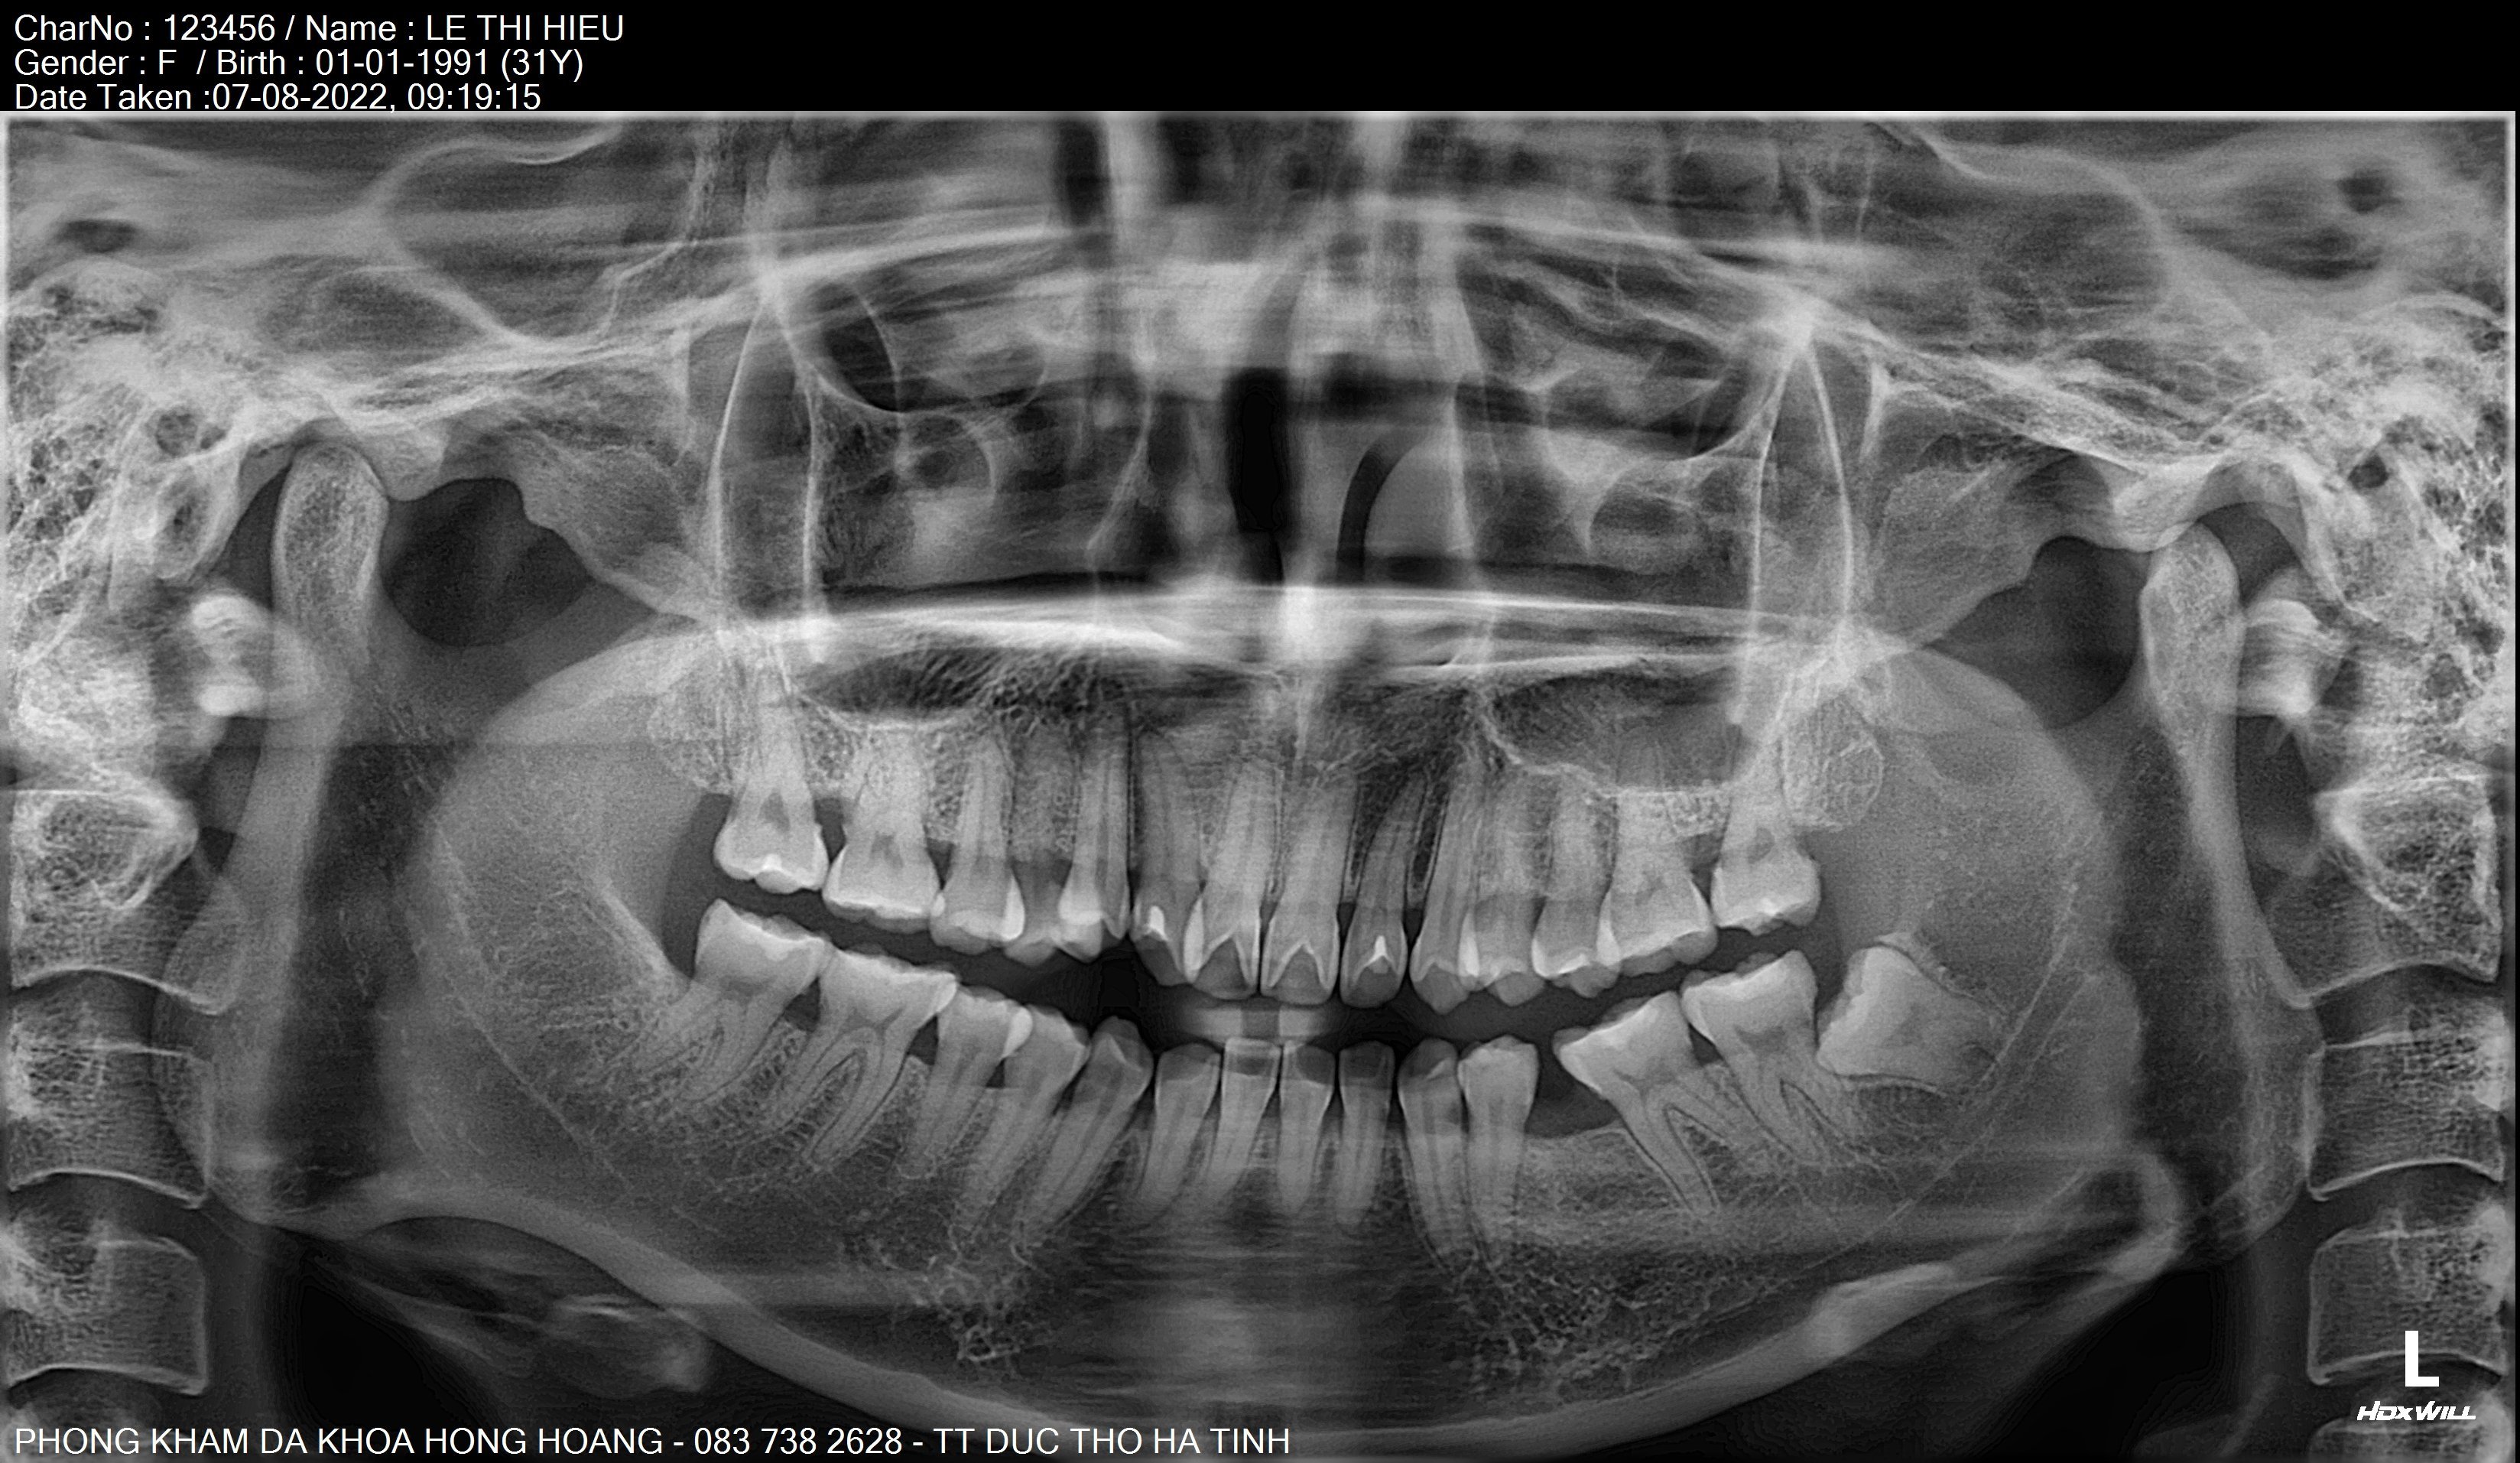

𝐇𝐈̀𝐍𝐇 𝐀̉𝐍𝐇 𝐂𝐇𝐔̣𝐏 𝐏𝐀𝐍𝐎𝐑𝐀𝐌𝐀 (𝐑𝐀̆𝐍𝐆 𝐓𝐎𝐀̀𝐍 𝐂𝐀̉𝐍𝐇) 𝐕𝐀̀ 𝐂𝐄𝐏𝐇𝐀𝐋𝐎 𝐁𝐀̆̀𝐍𝐆 𝐌𝐀́𝐘 𝐂𝐇𝐔̣𝐏 𝐂𝐀̆́𝐓 𝐋𝐎̛́𝐏 𝐕𝐈 𝐓𝐈́𝐍𝐇 𝐑𝐀̆𝐍𝐆 𝐇𝐀̀𝐌 𝐌𝐀̣̆𝐓.

🍀Hình ảnh chụp phim panorama và cephalo (mặt thẳng, mặt nghiêng) giúp bác sỹ răng hàm mặt đánh giá phân tích được khung hàm trên của bệnh nhân và lập kế hoạch điều trị chuẩn xác.

- Toàn cảnh ( panorama) : giúp nhìn thấy các trục chân răng, răng ngầm, các bệnh lý trong xương, tương quan lồi cầu 2 bên, hình dạng lồi cầu, các răng bệnh lý.